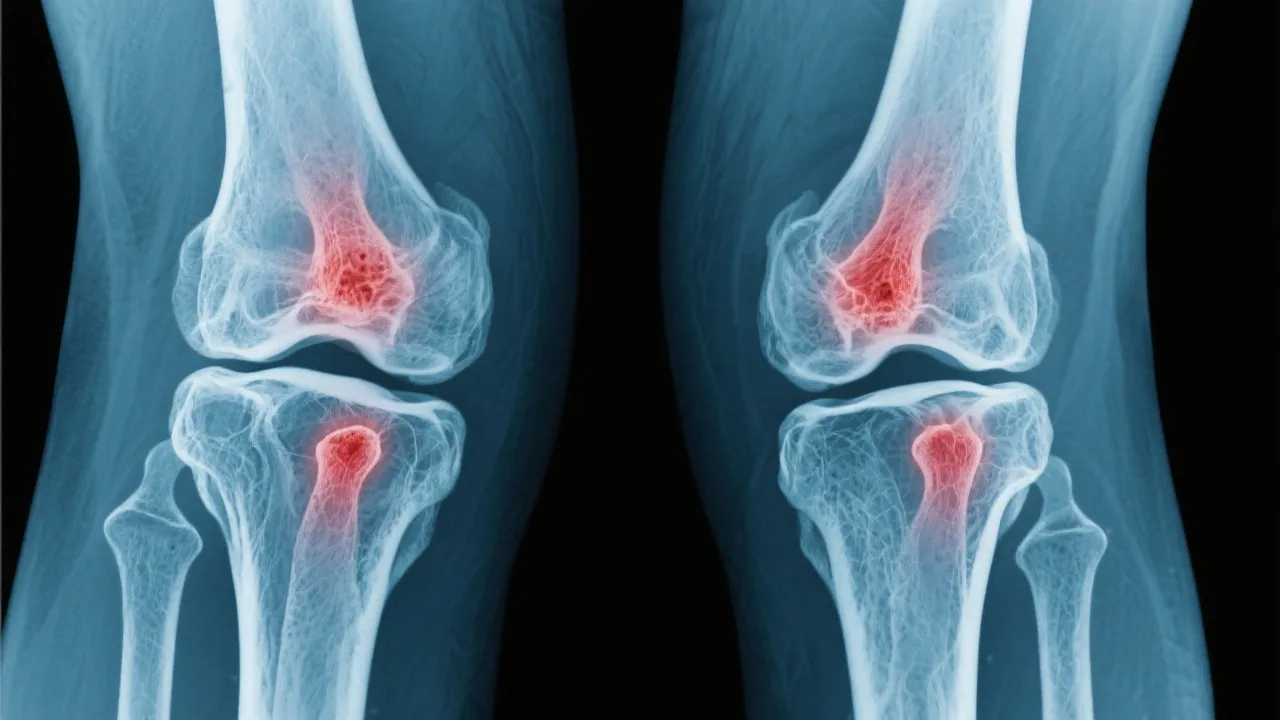

Addressing arthritis joint pain involves a detailed understanding of various treatment options designed to alleviate discomfort and improve quality of life. This article navigates through the landscape of arthritis treatment, exploring medical insights and evidence-based approaches to manage joint pain effectively. Examining arthritis, a prevalent condition impacting many, we dissect various methodologies employed to counteract the debilitating effects of joint inflammation.

Arthritis, a term encompassing over 100 different conditions, primarily involves inflammation of the joints. This condition is characterized by pain, stiffness, and swelling, which can significantly impair daily activities and quality of life. As individuals age, the prevalence of arthritis increases, making it a common concern among the elderly, though it can affect younger demographics as well. Arthritis can manifest in various forms and can impact not only the joints but also other organs in the body, causing systemic symptoms and complications. It is crucial to understand the underlying pathophysiology of arthritis to better appreciate how it affects individuals’ daily lives and the complexities involved in its management.

The very common types of arthritis include osteoarthritis, rheumatoid arthritis, and gout. Each type has distinct characteristics and requires tailored approaches to treatment: